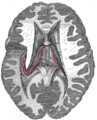

The fibers begin in the hippocampus on each side of the brain as fimbriae; the separate left and right sides are each called the crus of the fornix (plural crura). The bundles of fibers come together in the midline of the brain, forming the body of the fornix. The lower edge of the septum pellucidum (the membrane that separates the lateral ventricles) is attached to the upper face of the fornix body.

The body of the fornix travels anteriorly and divides again near the anterior commissure. The left and right parts separate, but there is also an anterior/posterior divergence.

- The posterior fibers (called the postcommissural fornix) of each side continue through the hypothalamus to the mammillary bodies; then to the anterior nuclei of thalamus, which project to the cingulate cortex.

- The anterior fibers (precommissural fornix) end at the septal nuclei and nucleus accumbens of each half of the brain.

The lateral portions of the body of the fornix are joined by a thin triangular lamina, named the psalterium (lyra). This lamina contains some transverse fibers that connect the two hippocampi across the middle line and constitute the commissure of fornix (also called the hippocampal commissure).

The terminal lamina creates the commissure plate. This structure gives existence to the corpus callosum, the septum pellucidum, and the fornix. The fornix splits into two columns at the front (anterior pillars), and then splits into two posterior crura. These two crura are joined together through the hippocampal commissure. The beginning of the splitting is called the psalterium or Lyra Davidis. The latter name is used because the structure resembles a lyra (or triangular harp): The two crura are the "chassis" of the lyra, and the commissure connections are the fibers.